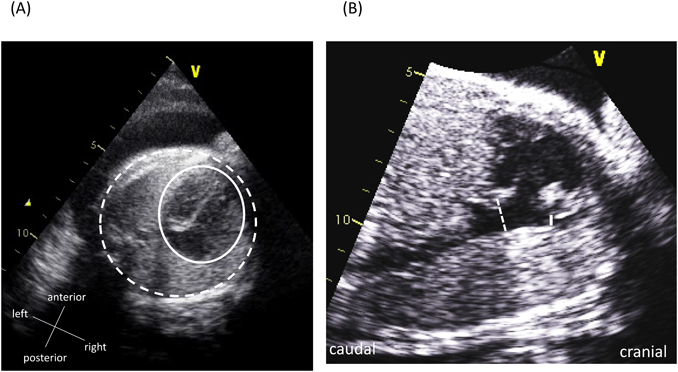

胎児心エコー所見をもとに早期娩出し救命できたハイリスク仙尾部奇形腫の胎児例Successful Preterm Delivery of a Fetus with High-risk Sacrococcygeal Teratoma Based on Fetal Echocardiographic Findings